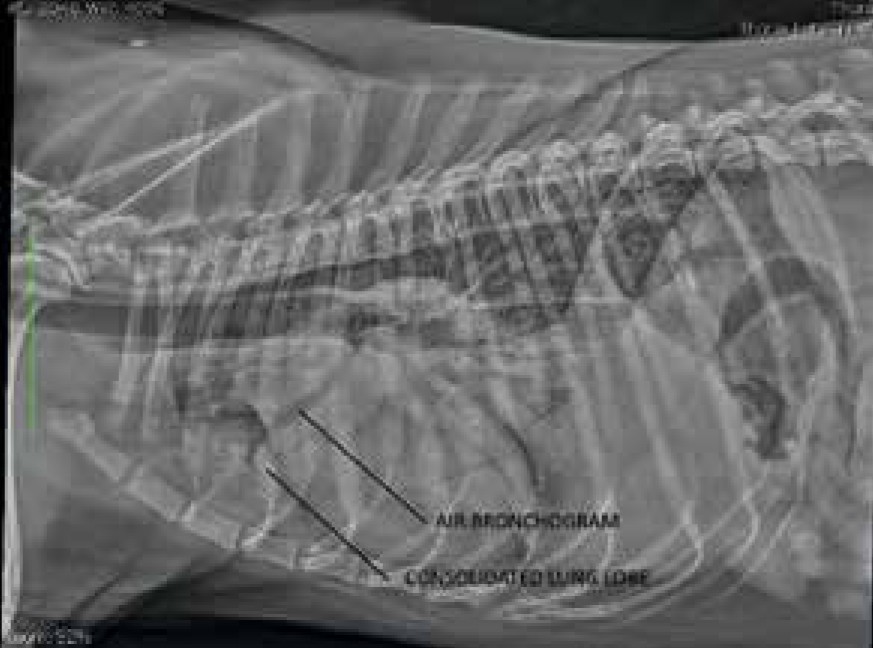

เปิด 5 สถิติน่ารู้ “ปอดอักเสบจากการสำลักในหมา” โรคเงียบที่มาพร้อมเสียงไอ (อัปเดท 2025)

เปิด 5 สถิติน่ารู้เกี่ยวกับโรคปอดอักเสบจากการสำลักในหมา พร้อมข้อมูลอาการ สาเหตุ วิธีวินิจฉัย และแนวทางรักษาเพื่อช่วยน้องหมารอดชีวิตได้ทันเวลา